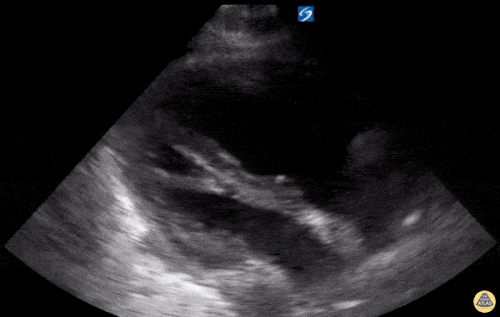

Sağ ventrikül fonksiyonunun değerlendirilmesi

Sağ ventrikül, önceki bölümde anlatılan temel kardiyak pencereler kullanılarak değerlendirilebilir. Normalde sağ ventrikül düşük basınçlı bir odacıktır ve sol ventriküle kıyasla daha küçük görünür.

Sağ ventrikül disfonksiyonunda özellikle şu bulgulara bakılır:

Sağ ventrikül dilatasyonu

Septal bombeleşme (septal bowing)

Kısa aks görüntüsünde, pulmoner arter basıncının artmasına bağlı olarak sağ ventrikül genişledikçe interventriküler septum sol kalbe doğru bombeleşir. Bu durum sol ventrikülde D-şekilli görünüm (D-sign) oluşturur.

Apikal dört boşluk görüntüsünde sağ ventrikül normalde sol ventrikülün yaklaşık üçte ikisi büyüklüğünde olmalıdır. Eğer iki ventrikül aynı boyutta görünüyorsa bu durum anormal kabul edilir ve dilatasyon düşündürür.

Bir diğer önemli bulgu McConnell belirtisidir. Bu bulgu, sağ ventrikül serbest duvarında hipokinezi bulunurken apeksin korunmuş olması şeklinde tanımlanır.

Önemli bir hata, sağ ventrikül disfonksiyon bulgularını otomatik olarak akut bir sürece (örneğin pulmoner emboli) bağlamaktır. Yukarıda belirtilen bulgular hem akut hem de kronik durumlarda görülebilir. Bu nedenle klinik bağlam ve hasta öyküsü önemlidir. Önceden yapılmış bir ekokardiyografi raporu, yatak başı değerlendirme ile karşılaştırma yapmak açısından çok yardımcı olabilir.

Apikal dört boşluk görüntüsü alınırken dikkatli olunmalıdır. Eğer görüntü aks dışı alınırsa sağ ventrikül kısalmış (foreshortened) görünebilir ve dilatasyon gözden kaçabilir. Bu hatadan kaçınmak için probu hafifçe döndürerek sağ kalbin en geniş göründüğü düzlemi yakalamak gerekir.